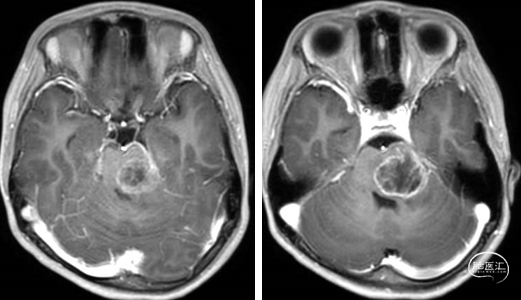

术前MRI

术后MRI